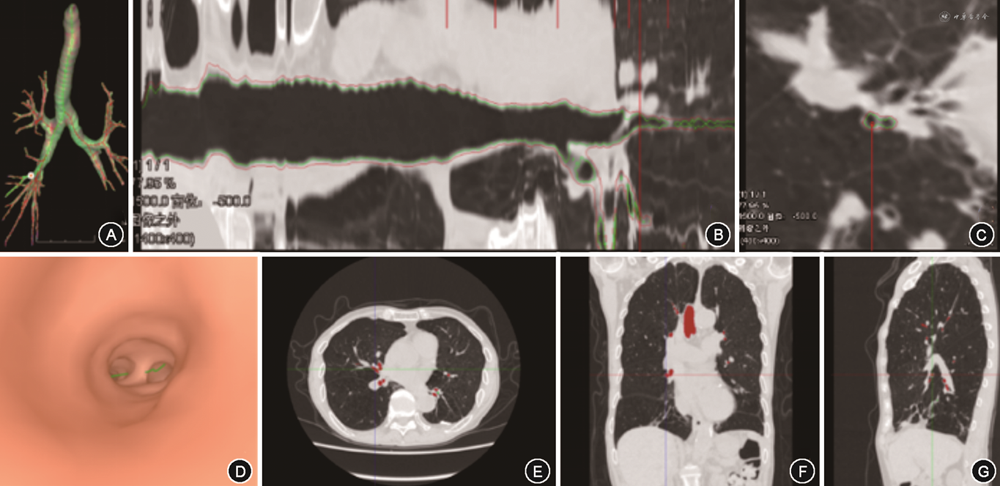

3.支气管参数:通过FACT智能几何技术自动分割支气管结构,得到支气管内外壁3D模型,并根据支气管3D模型处理得到支气管骨架,即支气管中线。支气管骨架为二叉树结构,分叉位置处由上级支气管分为两根下级支气管。气管标记为第0代,到分叉位置处分为第1代支气管,即左主支气管和右主支气管,依次类推,第3代为肺叶支气管,第4~6代为段及亚段支气管。两个分叉位置之间或分叉到远端端点之间的支气管为一个支气管分支。该软件对每个支气管分支自动进行全程测量,同一代的所有支气管分支参数取平均值得到该代的支气管参数。支气管内骨架点位置处,根据骨架方向,获得垂直于骨架方向的截面。利用已获得的内外壁结构和截面位置,计算得到4~6代支气管管壁厚度(4~6 thickness,4~6 T)、管壁面积百分比(4~6 wall area percent,4~6 WA%),同一支气管截面上管壁面积占支气管总面积的百分比截面参数(图2)。